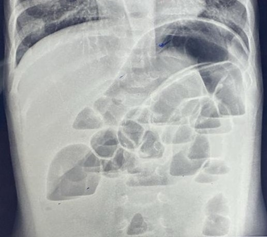

In infants under one year of age, the normal gas pattern on an abdominal X-ray appears honeycomb or polygonal shaped throughout the abdomen (Figure 1).3,4

Figure 1 Anteroposterior supine radiograph in a normal neonate on day-3 of birth showing honeycomb or polygonal gas pattern throughout the abdomen with gas visible in the rectum. It is difficult to differentiate small from large intestine in the neonatal period.